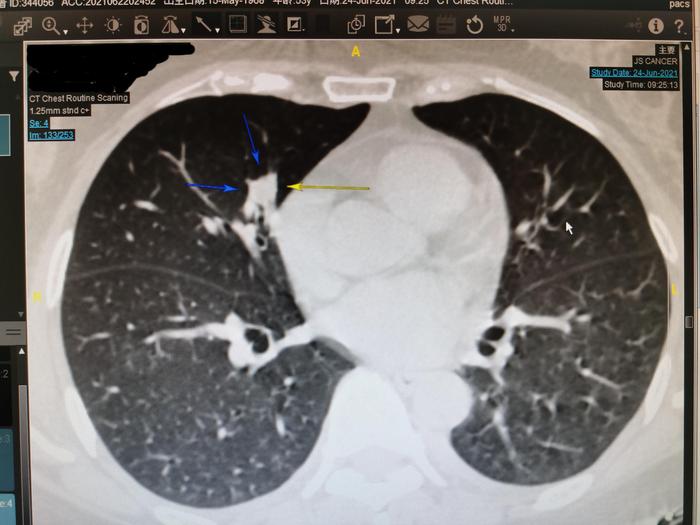

我用三个箭头指示这个右中肺实性结节,在薄层CT133层面,此结节的三条边都比较直。边缘笔直是良性结节的特点。